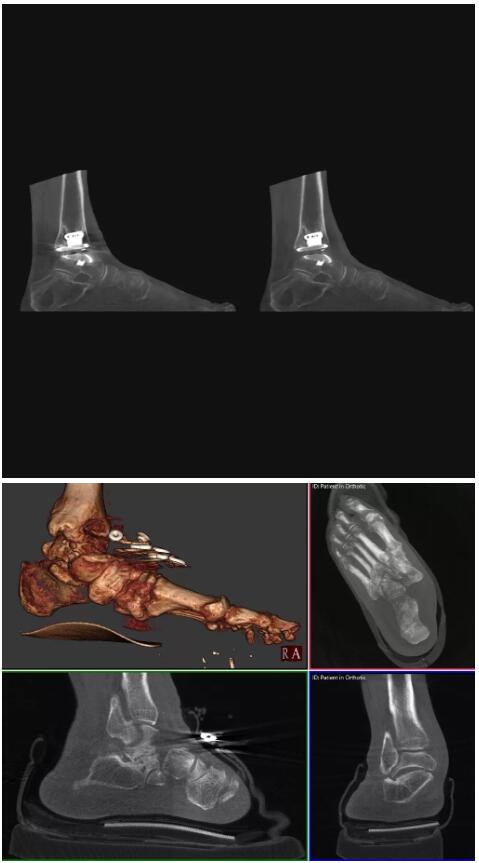

比如上面這款專用于足部和踝部掃查的CT成像系統(tǒng),患者在進(jìn)行CT掃查時(shí)只需要站在上面即可,雙腳站或者單腳站都可以,當(dāng)然,如果患者不是那么方便站著做完CT掃查,也可坐在上面。

這款CT掃查系統(tǒng)自帶屏蔽裝置,它的體積非常小,僅需要極小的空間即可,并不像常規(guī)CT那樣需要一間單獨(dú)的檢查室。此外,這種CT掃查的速度非???,僅需30秒左右可以完成檢查,輻射劑量相對(duì)常規(guī)的CT要少許多,尤其適合醫(yī)院的骨科使用。

而患者站著做足部或者踝部做CT檢查還有個(gè)好處是,可以檢查患者在負(fù)重的情況下,骨關(guān)節(jié)的真實(shí)情況,而躺著做CT掃查時(shí)未必能看出來(lái)。負(fù)重CT掃查特別是對(duì)于受傷的運(yùn)動(dòng)員或者舞蹈員來(lái)說(shuō)意義更大,能夠更準(zhǔn)確地評(píng)估傷情,幫助他們盡早復(fù)原。

以上介紹的CT均來(lái)自國(guó)外同一家公司,這些CT均配置了可視化軟件,可以進(jìn)行切片、3D重建以及大型CT附帶的所有典型的操作功能。

以下是這些“特立獨(dú)行”的CT所拍出來(lái)的圖像: